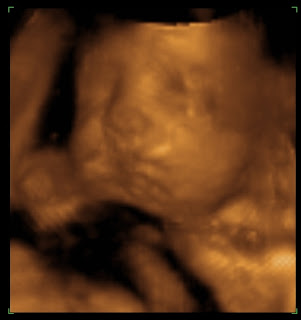

BTW, I think they are pretty cute:

Baby A

Baby B